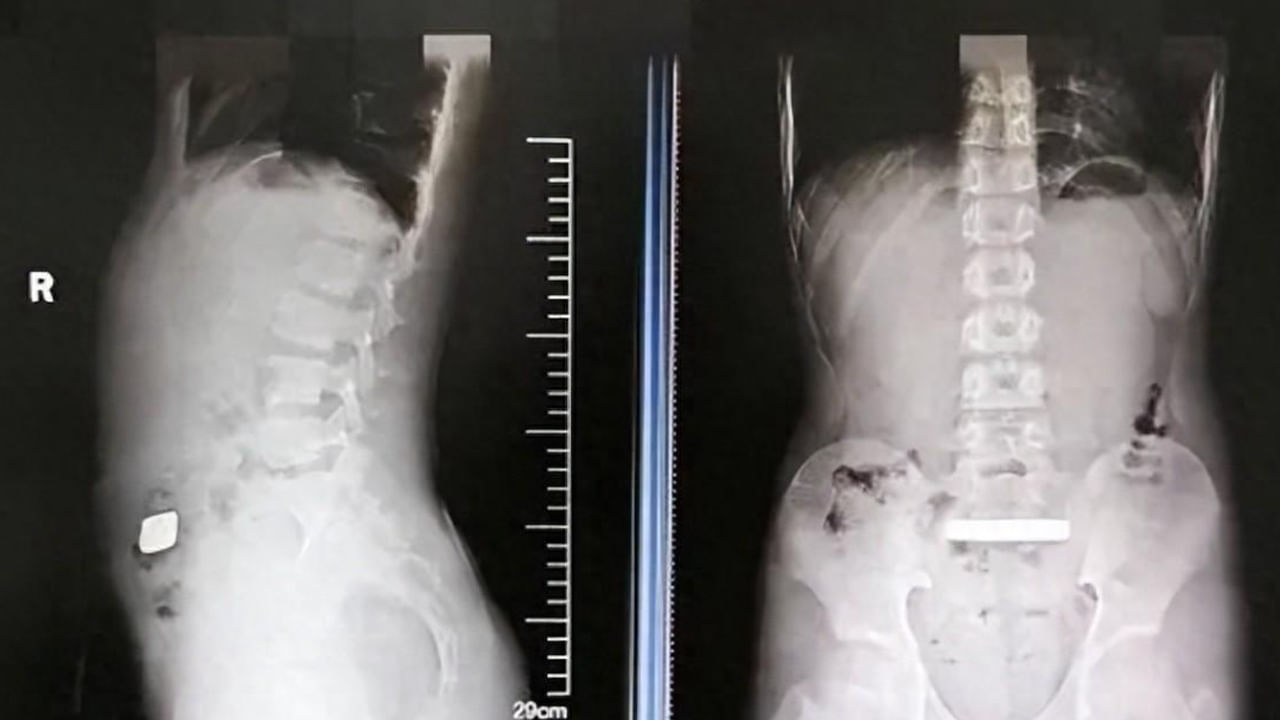

అది చైనాలోని జియాంగ్సు ప్రావిన్స్ ప్రాంతం. స్థానికంగా నివశించే ఓ బాలుడి పొత్తి కడుపు ఉబ్బుగా ఉండటం చూసి అతని తల్లిదండ్రులు ఆందోళన చెందారు. పిల్లోడికి నొప్పి, అసౌకర్యం లేనప్పటికీ.. ఎందుకైనా మంచిదని సుజౌ విశ్వవిద్యాలయ అనుబంధ పిల్లల ఆసుపత్రికి తీసుకెళ్లారు. అక్కడి వైద్యులు ఎక్స్-రే తీయగా బాలుడి కడుపులో ఒక ఘన లోహ వస్తువు చిక్కుకున్నట్లు గుర్తించారు. మరింత విశ్లేషణ కోసం స్కాన్ తీయగా.. లోపల ఆశ్చర్యకర రీతిలో దాదాపు 100 గ్రాముల బరువున్న బంగారు కడ్డీ ఉందని నిర్ధారించారు. కేసును పరిశీలించిన సీనియర్ డాక్టర్లు.. ఆపరేషన్ అవసరం లేకుండా.. ఆ కడ్డీ మలం ద్వారా బయటకు వచ్చేందుకు మెడిసిన్ ఇచ్చి పంపారు. రెండు రోజుల తర్వాత మళ్లీ ఆస్పత్రికి రాగా స్కాన్లో ఆ కడ్డీ కొంచెం కూడా కదలకపోవడాన్ని గమనించారు. దీంతో మరి ఎక్కువకాలం ఆ కడ్డీ అలానే ఉంటే.. లోపల ఇంటర్నల్ డ్యామేజ్ జరుగుతుందని భావించి.. సర్జరీ చేయాలని నిర్ణయించారు.

ఇద్దరు సర్జన్లు బాలుడికి ఎండోస్కోపిక్ సర్జరీ చేశారు. ఈ ప్రక్రియ కేవలం 30 నిమిషాలు మాత్రమే కొనసాగింది. ఎటువంటి ప్రమాదం లేకుండా బాలుడి కడుపు నుంచి బంగారు కడ్డీని విజయవంతంగా తొలగించారు. ఆపరేషన్ తర్వాత బాలుడు వెంటనే కోలుకున్నాడు. రెండు రోజుల్లోనే ఎప్పటిలాగా ఆహారం తీసుకోవడం ప్రారంభించాడు. లోపల ఎలాంటి ఇబ్బంది లేదని కన్ఫామ్ చేసుకున్నాక.. డాక్టర్లు ఆ చిన్నోడిని డిశ్చార్జ్ చేశారు.